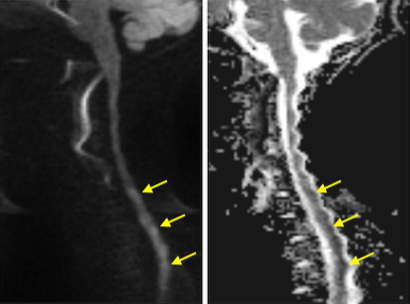

Results: An 11yo F presented with sudden onset back pain and lower extremity sensory disturbances following an ATV ride that quickly evolved into an ascending paralysis with associated urinary retention. Exam showed 4/5 strength in proximal UEs, 2/5 grip strength on the right, and 0/5 strength in LEs with associated areflexia and decreased sensation to light touch and pinprick but preserved vibratory sense. CSF studies were unremarkable with no albuminocytologic dissociation or lymphocytic pleocytosis. EMG/NCS revealed absent F-waves consistent with possible early demyelinating polyradiculopathy. She was started on IVIG given concern for AIDP. Extensive work-up including TSH, ESR, CRP, B1, B12, heavy metals, C. jejuni Ag, stool cx, blood cx, ANCA vasculitis panel, RMSF and Arbovirus Abs, and AchR and MuSK Abs was unremarkable. MRI revealed diffusion restriction in the cervicothoracic cord without enhancement (Fig 1). She had no improvement of her symptoms after completing 5 days of IVIG. She also developed long-tract signs including +Babinski on the left and LE spasticity. Repeat imaging 4 days from prior revealed adjacent vertebral body with area of T2 hyperintensity concerning for bony infarct (Fig 2). Given her rapid onset of symptoms, lack of improvement after treatment with IVIG, and development of long-tract signs, she was given a diagnosis of spinal cord infarction. FCE was deemed the etiology given the presence of adjacent bony infarct suggesting embolic phenomenon and the lack of evidence of CNS inflammation, infection, or other etiology. Repeat EMG/NCS showed evidence of severe reduction in the amplitudes of the compound motor action potentials which can be seen in compromise of the motor neuron population due to spinal cord infarction (Fig 3). She was discharged to inpatient rehab.